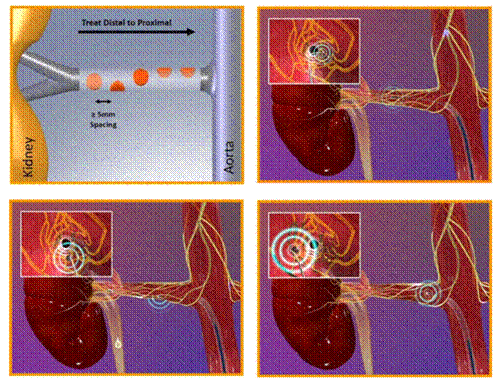

Hình 3: Lược đồ kỹ thuật trong nghiên cứu Symplicity HTN 1-2

Symplicity HTN-1 (catheter-based renal sympathetic denervation for resistant hypertension: a multicentre safety and proof-of-principle cohort study) là nghiên cứu đầu tiên về tính khả thi, tính an toàn và hiệu quả trên người của phương pháp triệt phá thần kinh giao cảm động mạch thận qua đường ống thông. Nghiên cứu được thực hiện trên nhiều trung tâm tại Australia, 45 bệnh nhân tăng huyết áp kháng trị đã được triệt đốt thần kinh giao cảm động mạch thận hai bên bằng năng lượng sóng tần số radio. Quy trình kỹ thuật trong Symplicity HTN-1: Các bệnh nhân sau khi thỏa mãn các tiêu chuẩn lựa chọn của nghiên cứu sẽ được chuẩn bị cho một thủ thuật thăm dò chảy máu và được chụp động mạch thận chọn lọc qua đường động mạch đùi. Sau đó, một ống thông dẫn (guide catheter) đường kính 8 French sẽ được luồn vào lỗ vào động mạch thận, qua đó, ống thông đốt với kích thước nhỏ hơn sẽ được đưa sâu vào trong động mạch thận để tiến hành triệt đốt thần kinh giao cảm từ phía nội mạch. Ống thông đốt với đặc điểm có thể điều khiển gấp duỗi được bởi bác sĩ thủ thuật (steerable) cho phép triệt đốt thành một đường xoắn ốc vòng quanh lòng động mạch thận từng bên. Cũng tương tự như quy trình triệt đốt các rối loạn nhịp tim bằng năng lượng tần số radio, quá trình đốt mạch thận được kiểm soát bởi các thông số nhiệt độ và điện trở nhằm đảm bảo năng lượng đủ để gây tổn thương mô, cắt đứt các đường dẫn truyền thần kinh giao cảm nhưng không tăng nhiệt độ quá cao gây tổn thương nội mạc làm hẹp động mạch thận. Trong Symplicity HTN-1, có 2 biến chứng liên quan đến thủ thuật được ghi nhận: 1 trường hợp lóc tách nội mạc mạch thận do đầu ống thông đốt. Động mạch thận bị lóc tách sau đó đã được đặt Stent; 1 trường hợp giả phình động mạch đùi do chọc mạch.

Ống thông đốt sử dụng trong các nghiên cứu Symplicity (Symplicity®, Flex-Catheter, Medtronic/Ardian Inc. USA) được thiết kế chuyên biệt cho triệt đốt trong lòng động mạch thận nhưng vẫn dựa trên nguyên lý sử dụng năng lượng tần số radio. Ngoài những ưu điểm vốn có vì được thiết kế chuyên biệt, nhược điểm của loại ống thông này là giá thành cao (xấp xỉ 7000 USD) nên khó có khả năng ứng dụng rộng rãi trên các bệnh nhân ở các nước thu nhập thấp trong đó có Việt Nam.